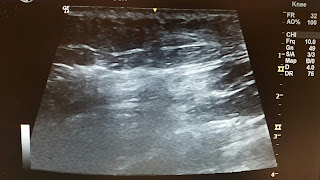

out what was going on. We did an ultrasound that showed that my FAVA hasn't

changed much for the past 8 months which was good news in a way but upsetting

because we didn't know what caused the flare-up! I had always had pain in two specific areas

in my butt/thigh so had always imagined that those were the only two FAVA spots

left since I had the gluteus maximus muscle removed from my amazing surgeon Dr.

Spencer, however I never realized that the disease is more complicated than

that. The ultrasound showed the FAVA was infiltrated throughout the majority of

my tissues in that area and that those two specific masses were extremely

inflamed to the point where it showed up like a black hole on the ultrasound.